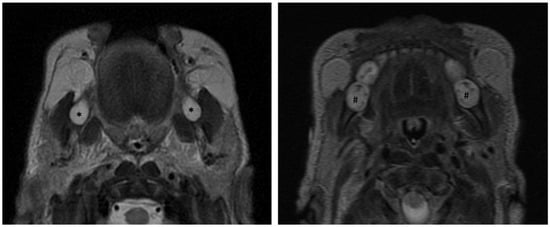

3.4. Application of Principles to Consecutive MR Exams